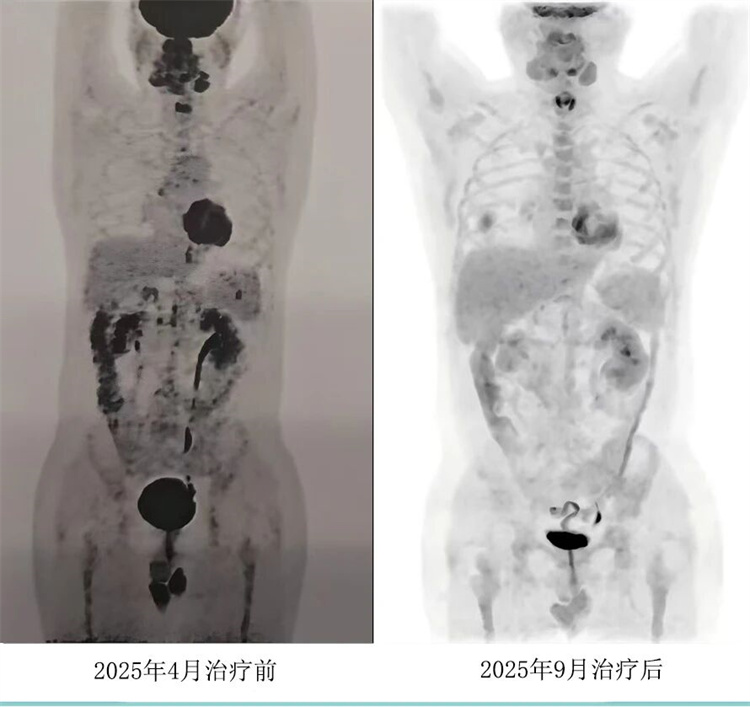

病例匯報環(huán)節(jié)由我院淋巴瘤科張薇醫(yī)生帶來了三例精彩紛呈的難治復(fù)發(fā)彌漫大B淋巴瘤CAR-T治療的病例。

病例過程跌宕起伏,從橋接治療到靶點(diǎn)的選擇,并發(fā)癥的處理都極具代表性。張醫(yī)生詳盡分享了患者在治療過程中的挑戰(zhàn)、決策依據(jù)以及CAR-T細(xì)胞治療后的驚人緩解與轉(zhuǎn)歸,充分展示了CAR-T技術(shù)為晚期患者帶來的突破性生存希望。